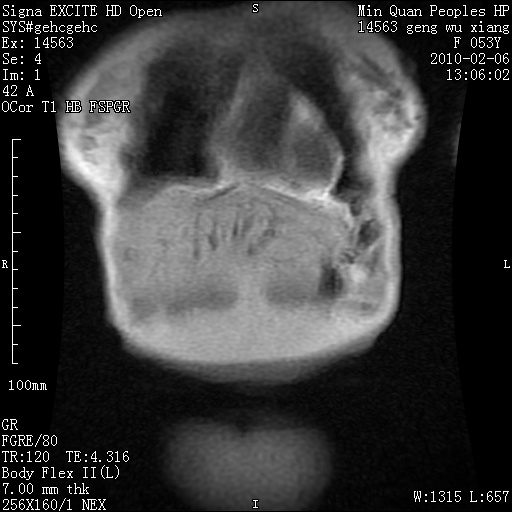

标题: MRI2762:胆道梗阻原因?

f,53y,全身黄染多日。

高位胆道梗阻 胆管癌可能性大

支持 高位胆道梗阻 胆管癌可能性大。